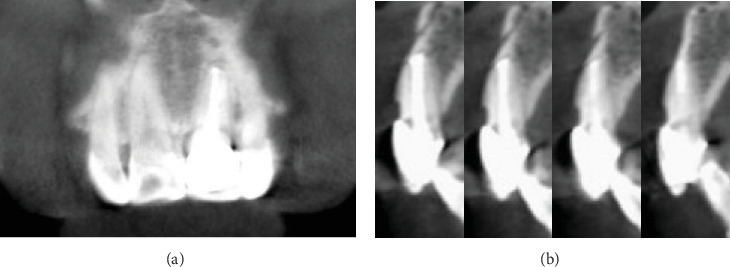

Crown-root fragment reattachment is an efficient method for restoring fractured teeth but is prone to failure due to complications such as microleakage or improper alignment, particularly when moisture control is compromised. In this case, the maxillary left central incisor that had sustained a complicated crown-root fracture was successfully reattached through a meticulously planned adhesive protocol. Specifically, precise visual reattachment on a small periodontal flap using the Super-Bond adhesive system in a controlled moisture led to favorable long-term results. The 55-month follow-up shows that conservative reattachment can restore function and appearance and preserve periodontal health.